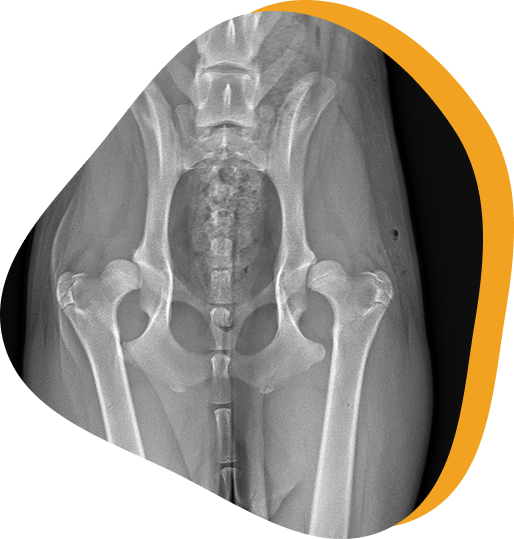

Hip dysplasia is an abnormal development and growth of the hip joint. Both hips are usually affected but symptoms may be more severe on one side. Hip dysplasia is manifested by varying degrees of laxity (looseness) of the hip joint with instability and malformation of the joint components. Arthritis is the long-term consequence of hip joint laxity.

Radiographs (X-rays)

We will perform calibrated radiographs to determine the appropriate size implants and evaluate each patient’s anatomy to confirm they

are a good candidate for the procedure.